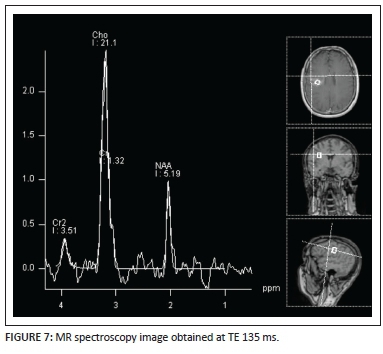

A MR spectroscopy image (Figure 7) performed at TE = 135 ms demonstrates a prominent choline peak with suppression of N-acetyl aspartate (NAA) and presence of a small lactate peak at 1.3ppm. A choline-to-NAA ratio greater than 2:1 is noted. This pattern is non-specific and can be seen in primary or metastatic tumours as well as in tumefactive demyelinating lesions.

Proton MR spectroscopy (MRS) is a powerful tool that is increasingly shown to be of value in molecular and metabolic neuroimaging. In TDL, elevated choline (Cho) peak is thought to represent a combination of demyelination, reactive astrogliosis and perivenular inflammation. The reduction in N-acetyl aspartate (NAA) seen in TDL represents cumulative axonal destruction and secondary neuronal mitochondrial dysfunction. The presence of lactate indicates a shift in cellular respiration from the oxidative metabolism of substrates to anaerobic glycolysis. This may be consequent on localised ischaemia, mitochondrial dysfunction and the inflammatory cascade. Typically, MRS of TDL may therefore reveal a brain metabolite pattern quite similar to that of gliomas with elevated choline, suppressed NAA, increased choline/creatine(Cr) ratio and presence of lactate and lipid peaks. This non-specific pattern is frequently seen in low-grade gliomas and TDL. Some authors8 have shown that, despite this considerable overlap in the patterns expressed by both entities, there is a difference in the NAA/Cr ratio, particularly centrally in TDL when compared with high-grade gliomas. TDL demonstrate a higher mean central NAA/Cr ratio owing to the lack of coagulative necrosis in the central aspect of TDL - a feature seen frequently in the centre of similar-sized gliomas.